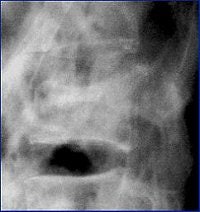

| Image G |

Cinnamon urged his fellow radiologists to consider offering 3D images to the surgeons. Surgeons often don't ask for 3D images, which can be very helpful for visualizing the fracture and treatment planning, he said.

The 0.5-mm slices offer fine bone detail, but pay a price on the soft-tissue images in terms of soft-tissue differentiation. Whereas the thicker (5-mm) slices fail to show the bone detail of the fracture well, but possess greater contrast resolution on the soft-tissue window to differentiate spinal cord from surrounding spinal fluid.